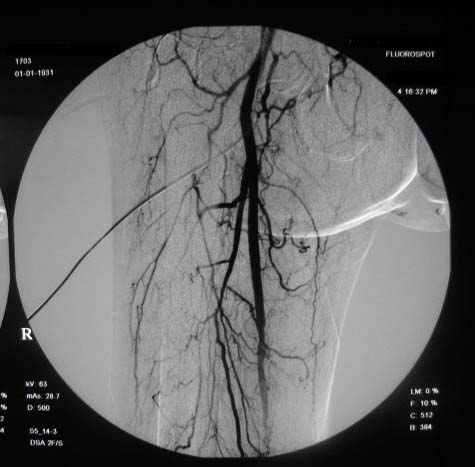

右下肢:

造影方法:取仰卧位,在局麻下,经右股动脉入路,采用改良seldingers技术,置入5f cobra导管于左髂外动脉行dsa,采集速度为2幅/秒,注射速率为6ml/秒,分节段造影;再将导管采用成襻技术放置于右侧髂外动脉,采用左侧同样的方法行dsa,术毕拔管、压迫止血约15分钟,包扎后嘱返病房,术后右足背动脉可扪及搏动。

右侧股浅动脉上、中段多处狭窄,下段闭塞。左侧股浅动脉多处狭窄,国动脉起始部狭窄。可以用球囊扩张配合动脉内溶栓或股浅动脉支架置入。多为糖尿病所致。